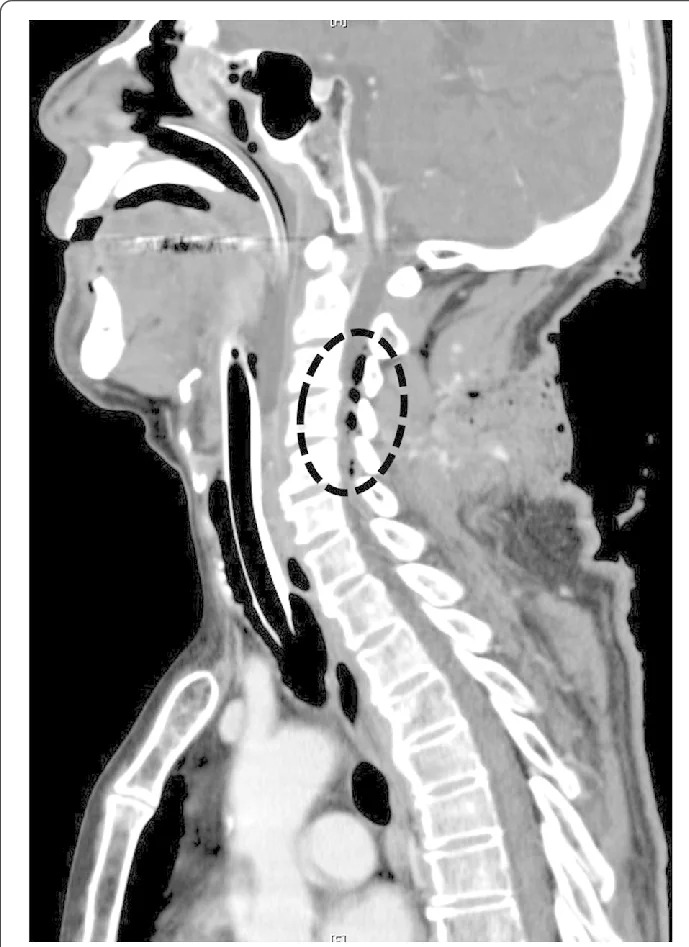

Fig 2: Computed tomography scan showing air in the spinal canal. The black circle indicates air in the spinal canal, suggesting dura mater perforation.

The need for immediate definitive airway management and surgical hemostasis was apparent. While several people maintained manual in-line stabilization and pressure hemostasis of his head and neck, anesthesia was induced in our ED. Alternative ventilation and intubation equipment, including a supraglottic airway device, video laryngoscope, and surgical airway device, was set up, and we performed rapid-sequence intubation (RSI) with intravenously administered fentanyl (1 μg/kg), ketamine (1 mg/kg), and rocuronium (1 mg/kg) using a conventional laryngoscope. Direct laryngoscopy provided a Cormack–Lehane grade 1 view and revealed neither airway distortion nor edema. An endotracheal tube (inner diameter, 7.0 mm) passed his vocal cords easily. Computed tomography revealed air in his spinal canal, suggesting that the dura mater was perforated (Fig. 2).